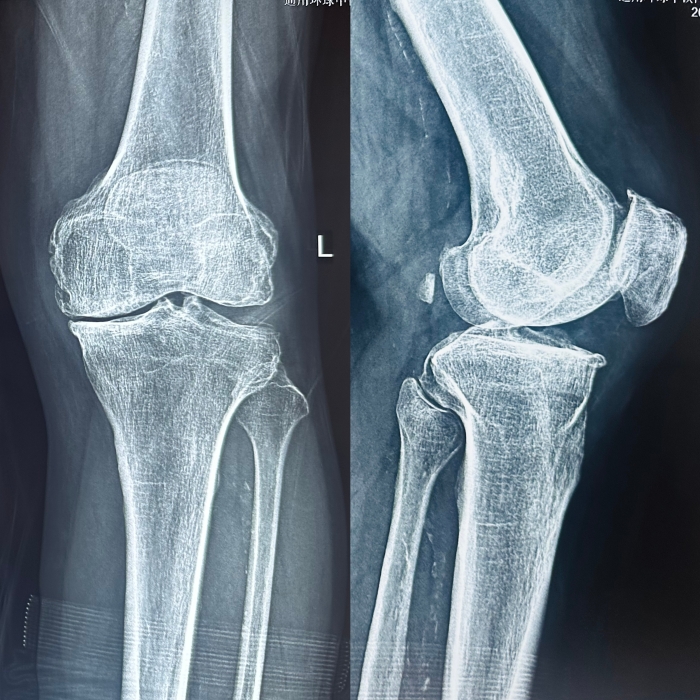

今年(nián)68歲的周叔,左膝關節疼痛、活動受限多年(nián),他(tā)曾嘗試過多種保守治療,但(dàn)效果不佳。飽受病痛折磨、嚴重影(yǐng)響日(rì)常生(shēng)活的周叔,爲徹底解決這一頑疾,決定進行手術(shù)治療。

經完善相(xiàng)關檢查,最終診斷爲膝關節退行性關節病。經過全面的評估和討(tǎo)論,姬傳磊決定實施骨科(kē)機(jī)器人(rén)輔助人(rén)工(gōng)膝關節置換手術(shù),并向周叔及家屬予以解釋,獲得(de)一緻同意。

術(shù)前